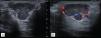

Se solicitaron radiografías simples (fig. 1), ecografía (fig. 2) y resonancia magnética (fig. 3).

La descripción ecográfica del TCGVT es una lesión hipoecoica, heterogénea, con Doppler, en relación con el tendón afectado. En resonancia se presenta como una lesión lobulada, de intensidad intermedia en T1 y T2, que en STIR muestran realce intenso. La determinación de focos de hemosiderina hipointensos es útil para diferenciar de otras lesiones.